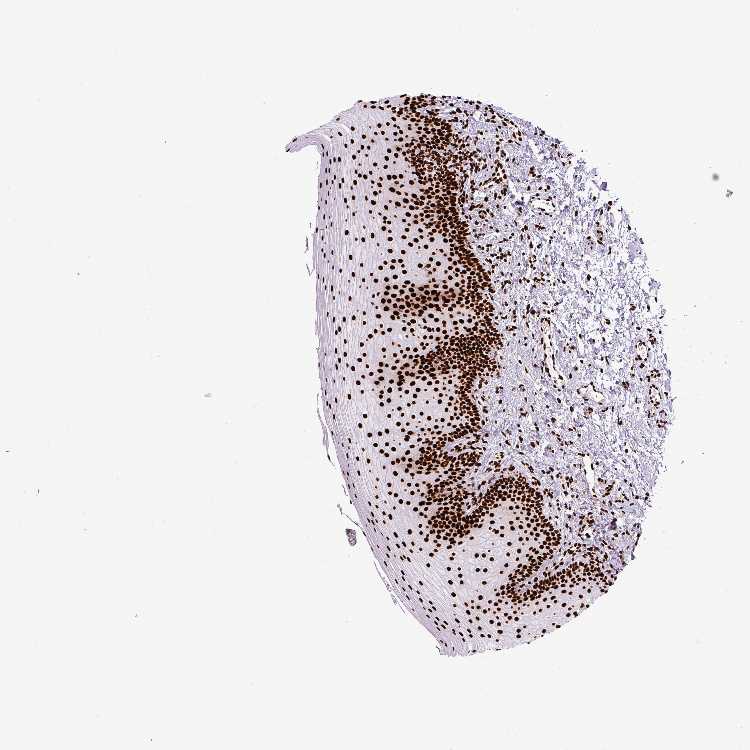

TISSUE PRIMARY DATA ORAL MUCOSA Show tissue menu

Oral mucosa

ORAL MUCOSA - Antibody stainingi

Antibody staining in the annotated cell types in the current human tissue is reported as not detected, low, medium, or high, based on conventional immunohistochemistry profiling in selected tissues. This score is based on the combination of the staining intensity and fraction of stained cells.

Each image is clickable and will lead to virtual microscopy that enables deeper exploration of all samples and also displays staining intensity scores, fraction scores and subcellular localization as well as patient and tissue information for each sample.

Antibody HPA008784Antibody CAB033036Antibody CAB058691

Squamous epithelial cells HighHighHigh